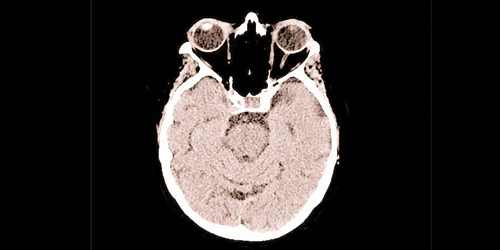

كشفت دراسة حديثة أن الذكاء الصناعي الجديد وتكنولوجيا التعلم العميق قد يكونان قادرين على اكتشاف مرض ألزهايمر مبكراً بدقة شبه مثالية.

وعمل فريق من جامعة كاوناس للتكنولوجيا (KTU) في ليتوانيا على بناء طريقة التحليل الجديدة، التي يُعتقد أنها تتضمن دقة تزيد عن 99 %.